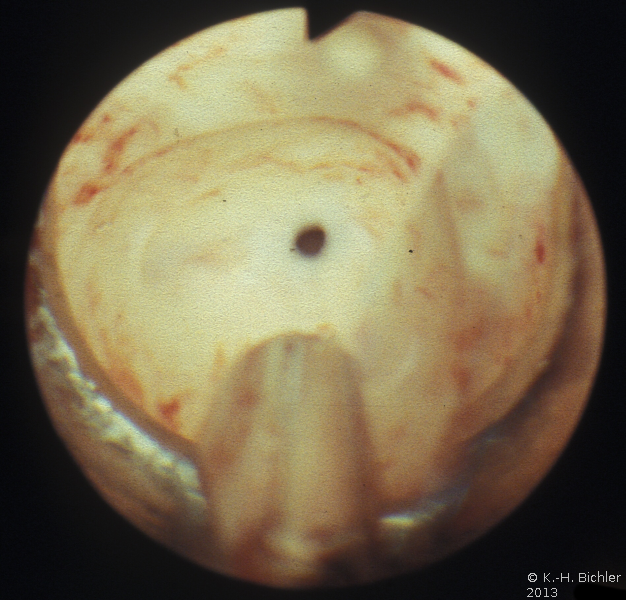

Die Abbildung zeigt das Verfahren der endoskopischen inneren Schlitzung bei Harnröhrenobstruktion (Abbildung 13).